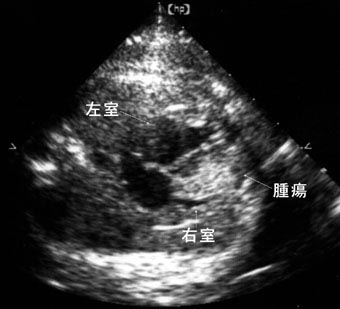

心臓腫瘍

右室内を満たすような高輝度の心臓腫瘍を認める。横紋筋腫であった。